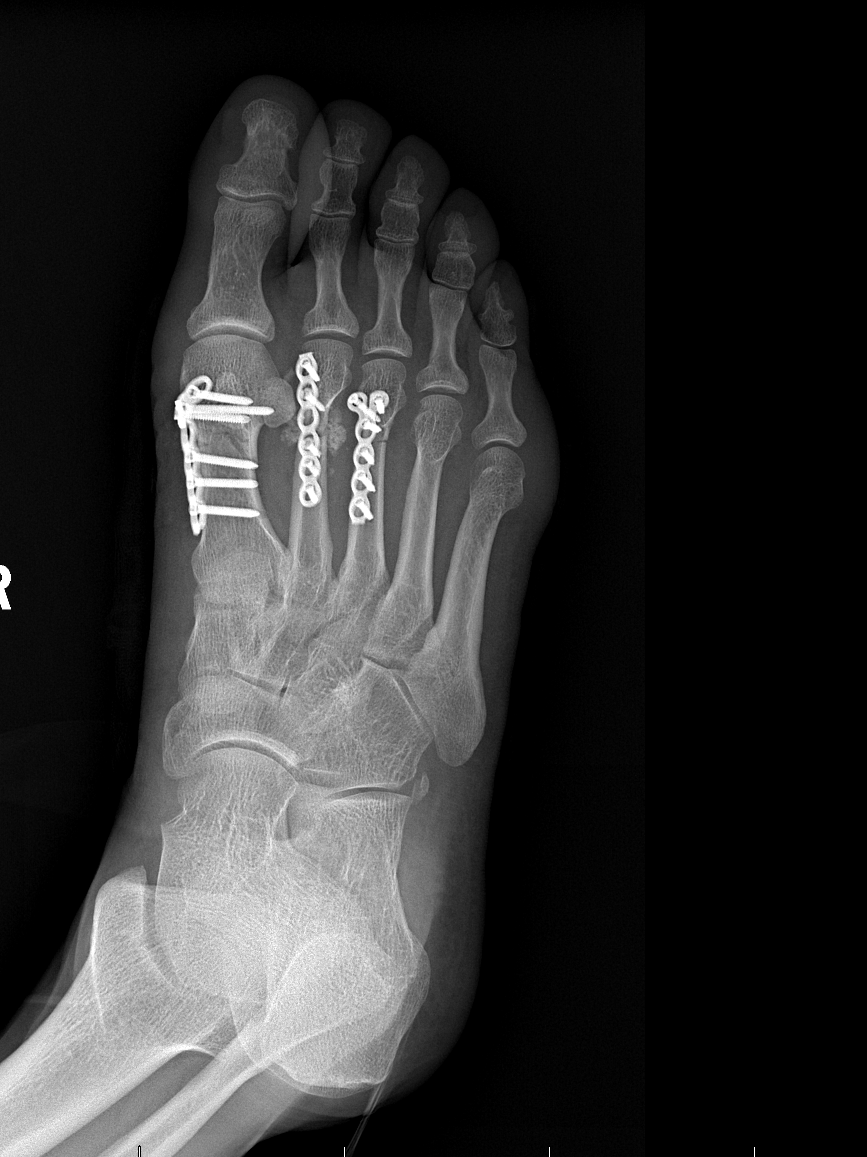

2025年4月18日,李先生因意外受伤来到玉溪市中山医院骨科就诊。经详细检查会诊,李先生被诊断为右侧开放性多发性足骨折、右足第1、2、3跖骨骨折。骨科团队迅速为李先生制定了个性化治疗方案,并于4月28日,由骨科副主任医师曾润华主刀,成功实施“跖骨骨折切开复位钢板内固定术”。手术后,医护人员每日密切关注李先生的病情,耐心指导他进行康复训练。在医护团队的精心照料下,李先生恢复良好,疼痛明显减轻,患部功能逐步恢复,于5月18日顺利出院。为表达感谢,李先生特意送来一面印有“医德高尚医术精,关爱病患暖人心”的锦旗,向曾润华医生及医护人员表达诚挚谢意。

患者术后X线影像